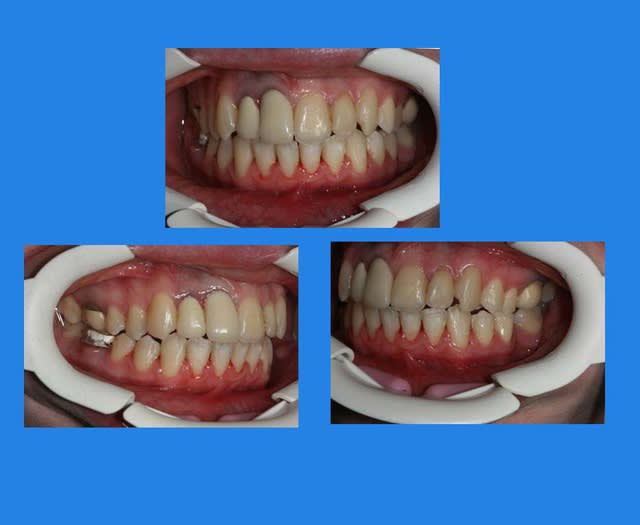

Voici le cas il y a un an

Elle était enceinte de 8 mois,

la voiture lui était déconseillée par son médecin,

j’ai donc décidé, avec l’accord de la patiente, de déposer (sans contention), car je ne voulais plus la laisser sans surveillance avec un matériel ortho en place

@+ Bjc.